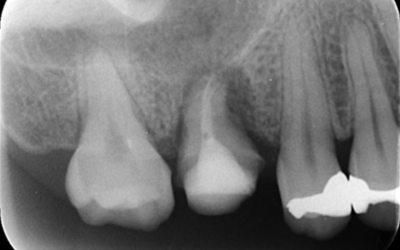

移植12ヶ月後のレントゲン

移植12ヶ月後。セラミッククラウンで歯冠を修復した。

デンタルX線写真では透過像もほぼ消失している。